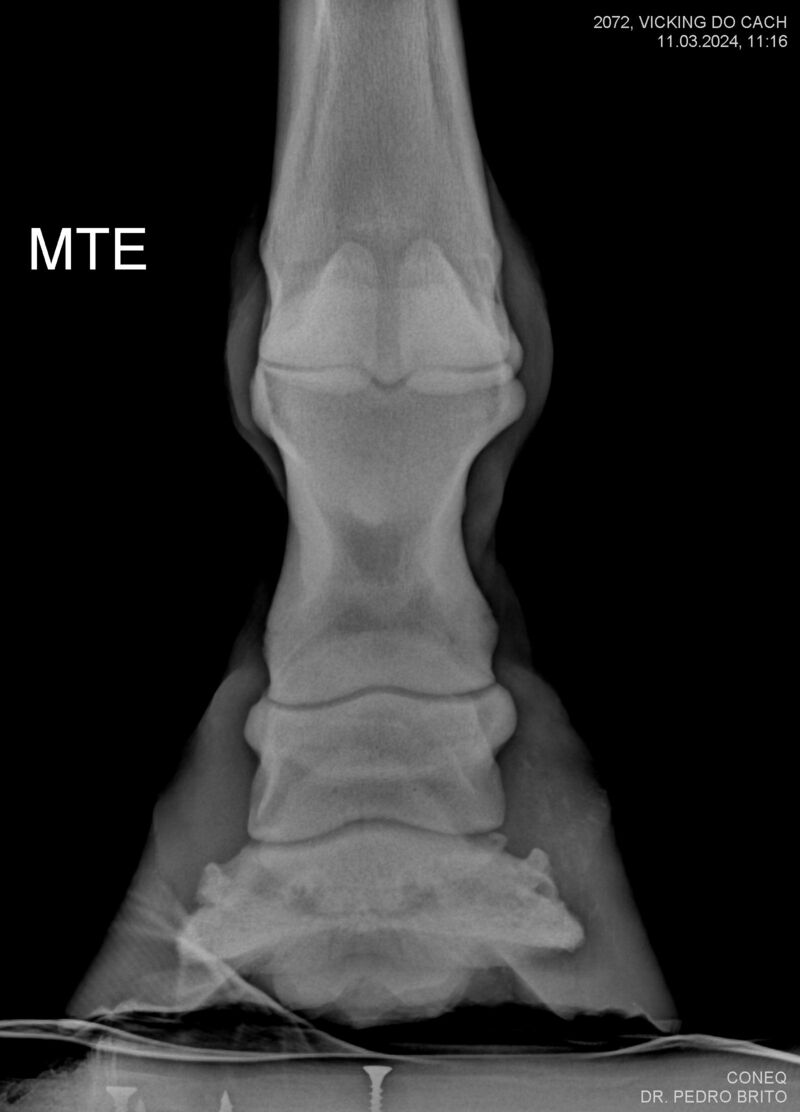

VIKING DO CACH